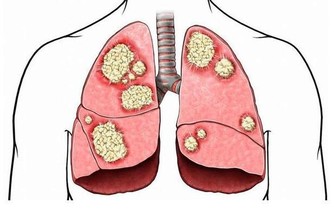

由於肝臟最忙最累,又由於肝臟面對有毒有害物質的侵襲,再由於肝髒又任勞任怨,所以肝臟最容易受到傷害,患病最多,也最難治,諸如,甲肝、乙肝、丙肝、黃疸型等等,酒精肝、脂肪肝、肝硬化等等。了解了肝臟的特點,我們就能應該善待和保護自己的肝臟。從醫藥學研究和臨床時間來看,目前大多數肝病是很難單純依靠藥物來治好的。能夠有效激活人體的免疫系統,調節肝臟代謝,清除體內毒素,幫助受損的肝細胞修復,有利於肝細胞生成。